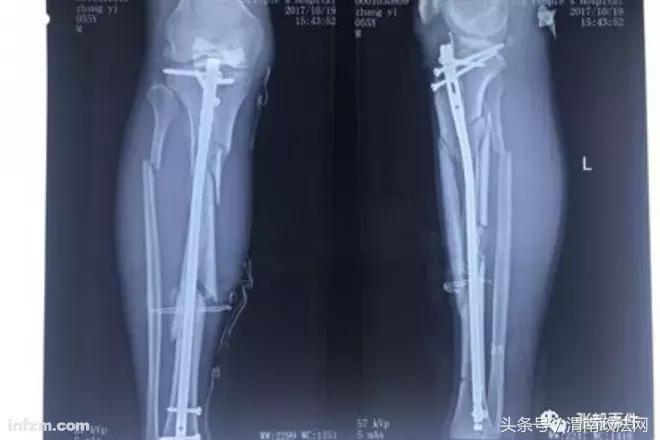

为了摆脱乱局,张毅开始自筹资金、寻找场地,以组建新医院。但在此期间,2017年10月18日,在张毅父母位于师范学院院内的家属楼下,张毅被4名驾驶无牌照黑色越野车的蒙面人打断右腿。X光片显示,被打后,张毅的两根胫骨和两根腓骨断成几截。尽管事发8天后,安次警方抓获4名犯罪嫌疑人,但此后在张毅住院治疗期间,其仍持续受到骚扰威胁。他称杨玉忠曾指使会计在未履行任何财务手续的情况下从医院挪用现金1100万元,又从自己的儿媳赵楠卡中转走500万元。

▲张毅右腿小腿粉碎性骨折,图为右小腿两个角度下的X光片。(南方周末记者 王宇/图)